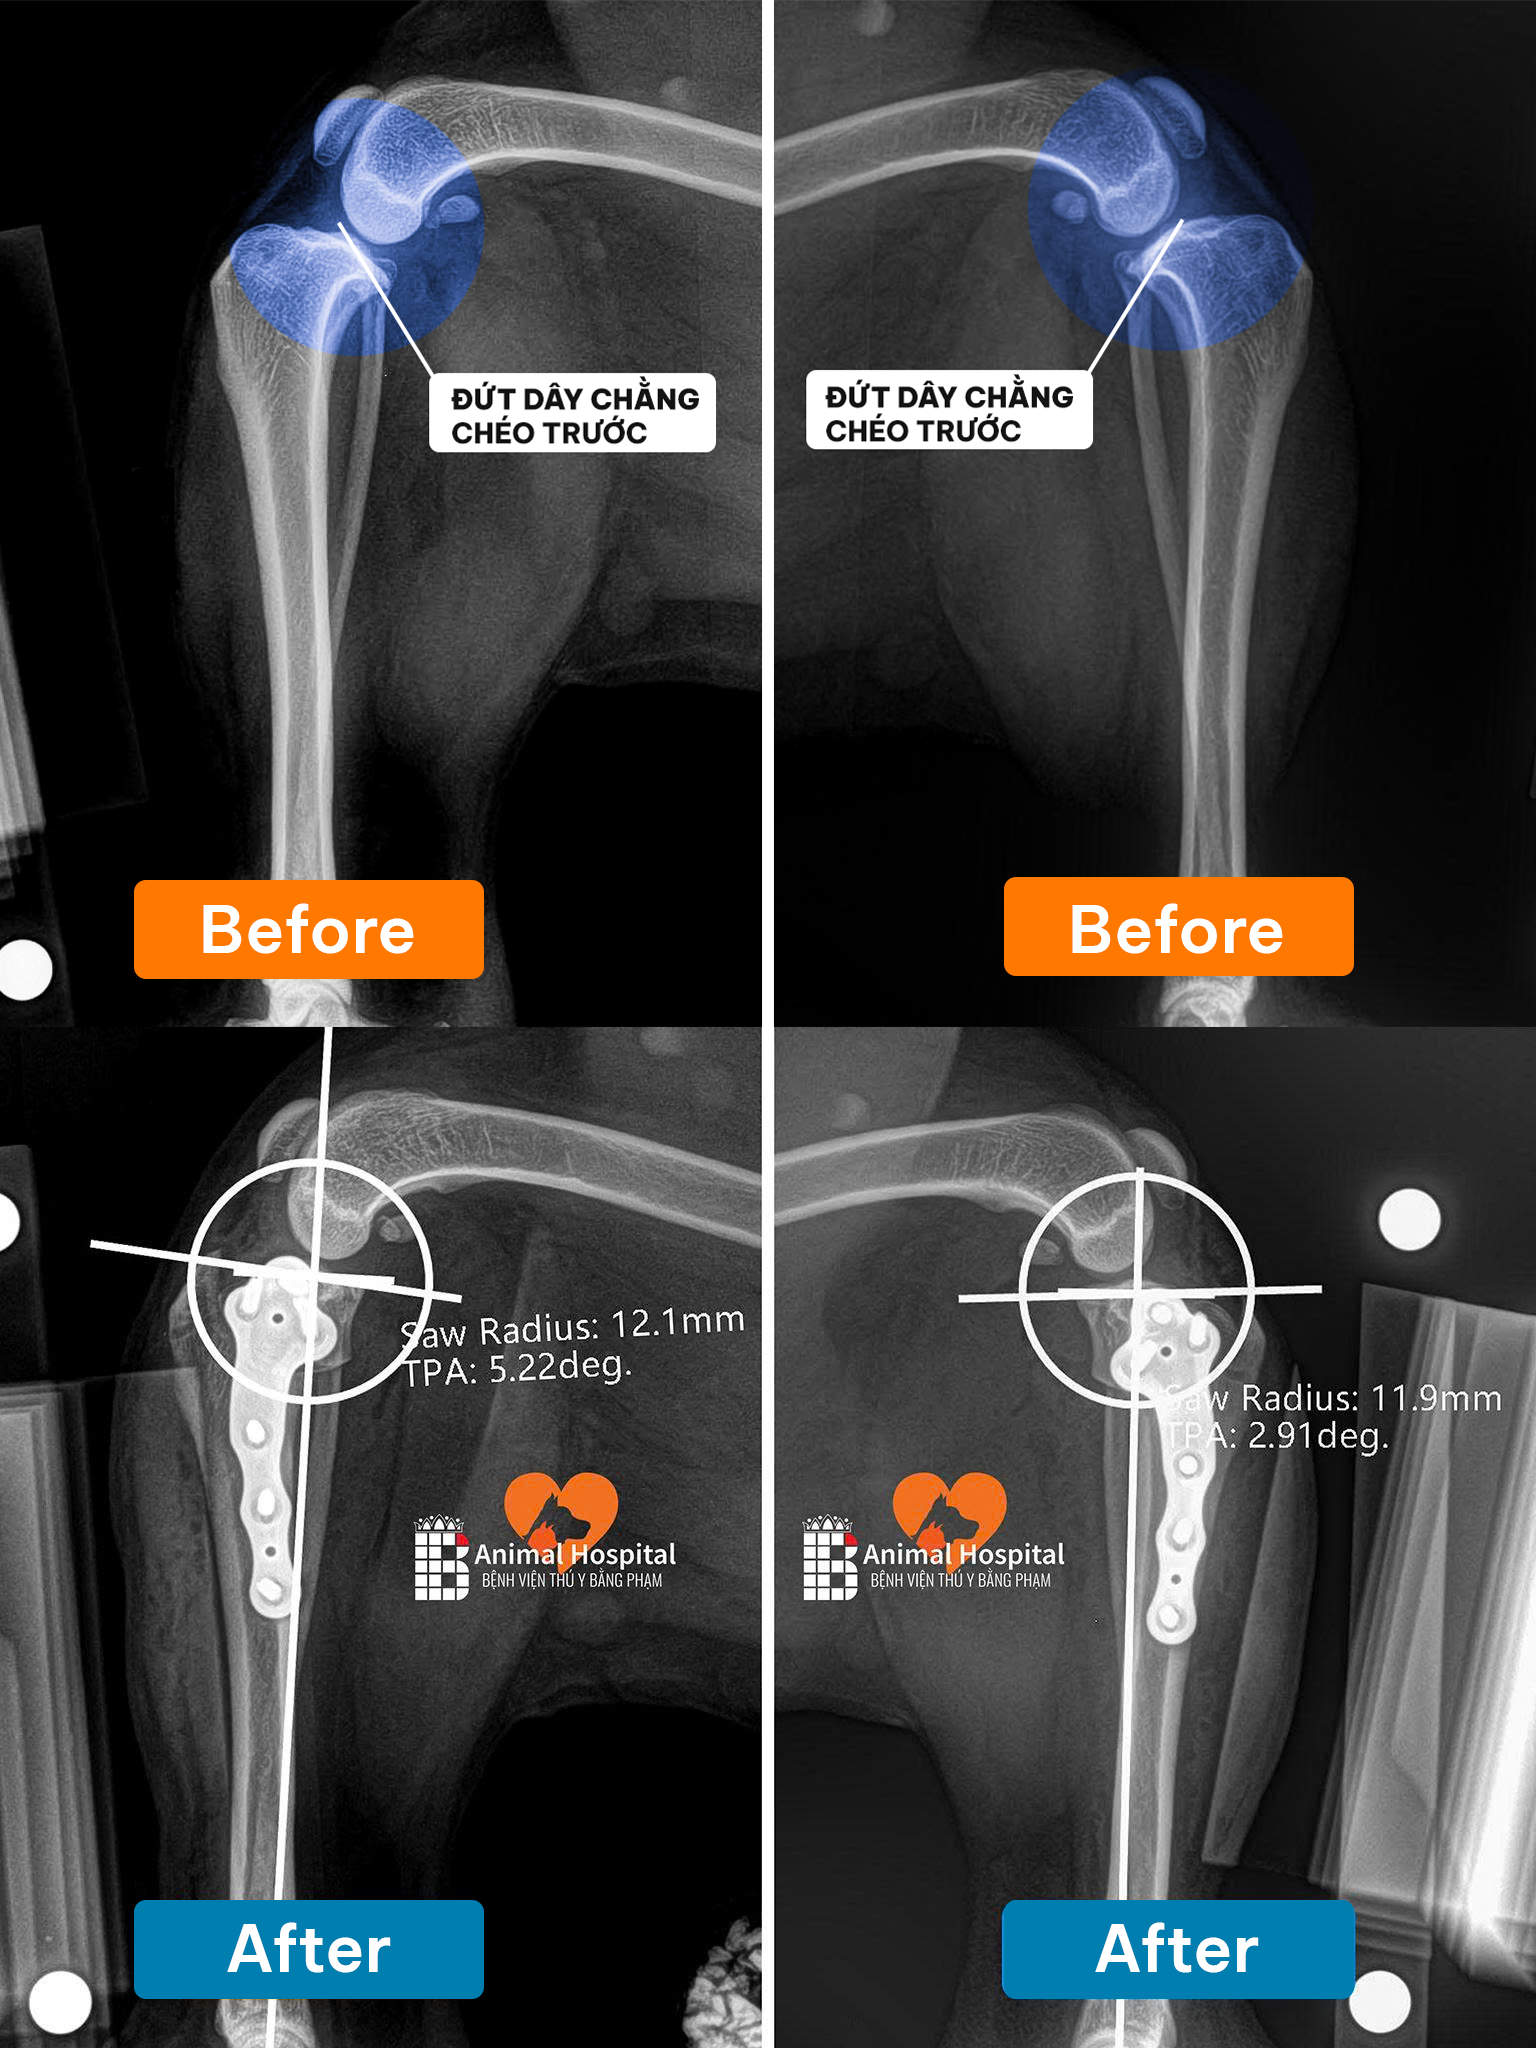

- Chụp X-quang (X-ray) để xác định chính xác vị trí và loại gãy xương (type of fracture).

- Nhấn mạnh: Phẫu thuật chỉnh hình xương (orthopedic surgery) đòi hỏi trang thiết bị chuyên biệt (thiết bị cố định bên trong/bên ngoài – internal/external fixation) và bác sĩ chuyên khoa.

Tại Bệnh viện thú y Bằng Phạm, đội ngũ bác sĩ chuyên khoa Ngoại – Chỉnh hình của chúng tôi sở hữu nhiều năm kinh nghiệm trong điều trị và phẫu thuật gãy xương cho chó mèo, bao gồm cả những ca phức tạp như gãy hở, gãy nhiều đoạn, hay trật khớp đi kèm tổn thương phần mềm.

Các bác sĩ đều được đào tạo chuyên sâu về phẫu thuật xương khớp và phục hồi chức năng thú y, với chứng chỉ BlueSAO quốc tế uy tín.